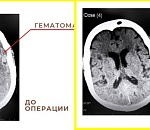

Врачи спасли 86-летнюю астраханку от тяжелого инсульта, удалив у нее огромную гематому https://punkt-a.info/news/novosti-kratko/vrachi-spasli-86-letnyuyu-astrakhanku-ot-tyazhelogo-insulta-udaliv-u-nee-ogromnuyu-gematomu

Скоро женщина может вернуться к нормальной жизни.